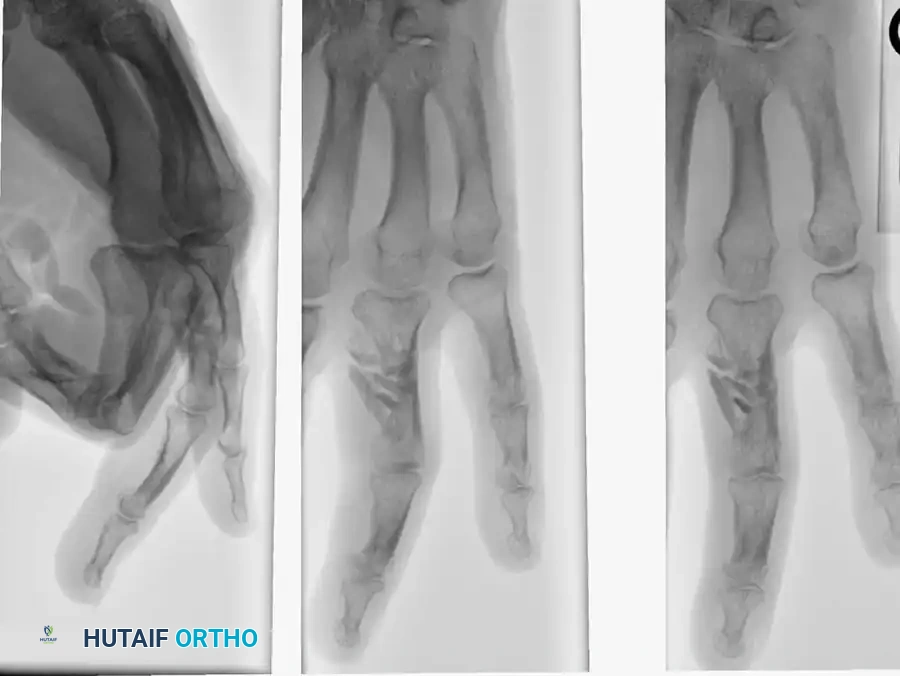

Fracture-Dislocations of the Proximal Interphalangeal (PIP) Joint

Fracture-dislocations at the PIP joint typically result in an unstable dorsal displacement of the middle phalanx. This is caused by the disruption of the volar plate's attachment to the volar lip of the middle phalanx, often accompanied by impaction of the articular surface.

Treatment is strictly dictated by the percentage of articular surface involved and the degree of comminution.

2. Small Volar Fragment (<50% of Joint Surface): Extension Block Splinting

If the fragment includes less than 50% of the articular surface and the joint can be concentrically reduced in flexion, the technique described by McElfresh, Dobyns, and O’Brien is the gold standard. This allows active motion of the PIP joint while maintaining the finger in an extension block splint.

Closed Reduction Technique (McElfresh, Dobyns, and O’Brien):

* Determine the exact angle of extension at which the PIP joint subluxates dorsally (the "instability angle") under fluoroscopy.

* Incorporate a malleable metal dorsal splint into a forearm gauntlet plaster cast.

* Position the splint so the involved finger is maintained in flexion at both the MCP and PIP joints.

* Block the PIP joint in flexion exactly 15 degrees short of the demonstrated position of instability.

* Ensure the proximal phalanx is held securely against the dorsal splint to prevent paradoxical extension at the PIP joint caused by further flexion of the MCP joint.

* Aftertreatment: Immediate active flexion of the PIP joint is permitted and encouraged. Full extension is blocked for 6 to 12 weeks; however, the splint is adjusted weekly to permit an increased amount of extension as the fracture heals.